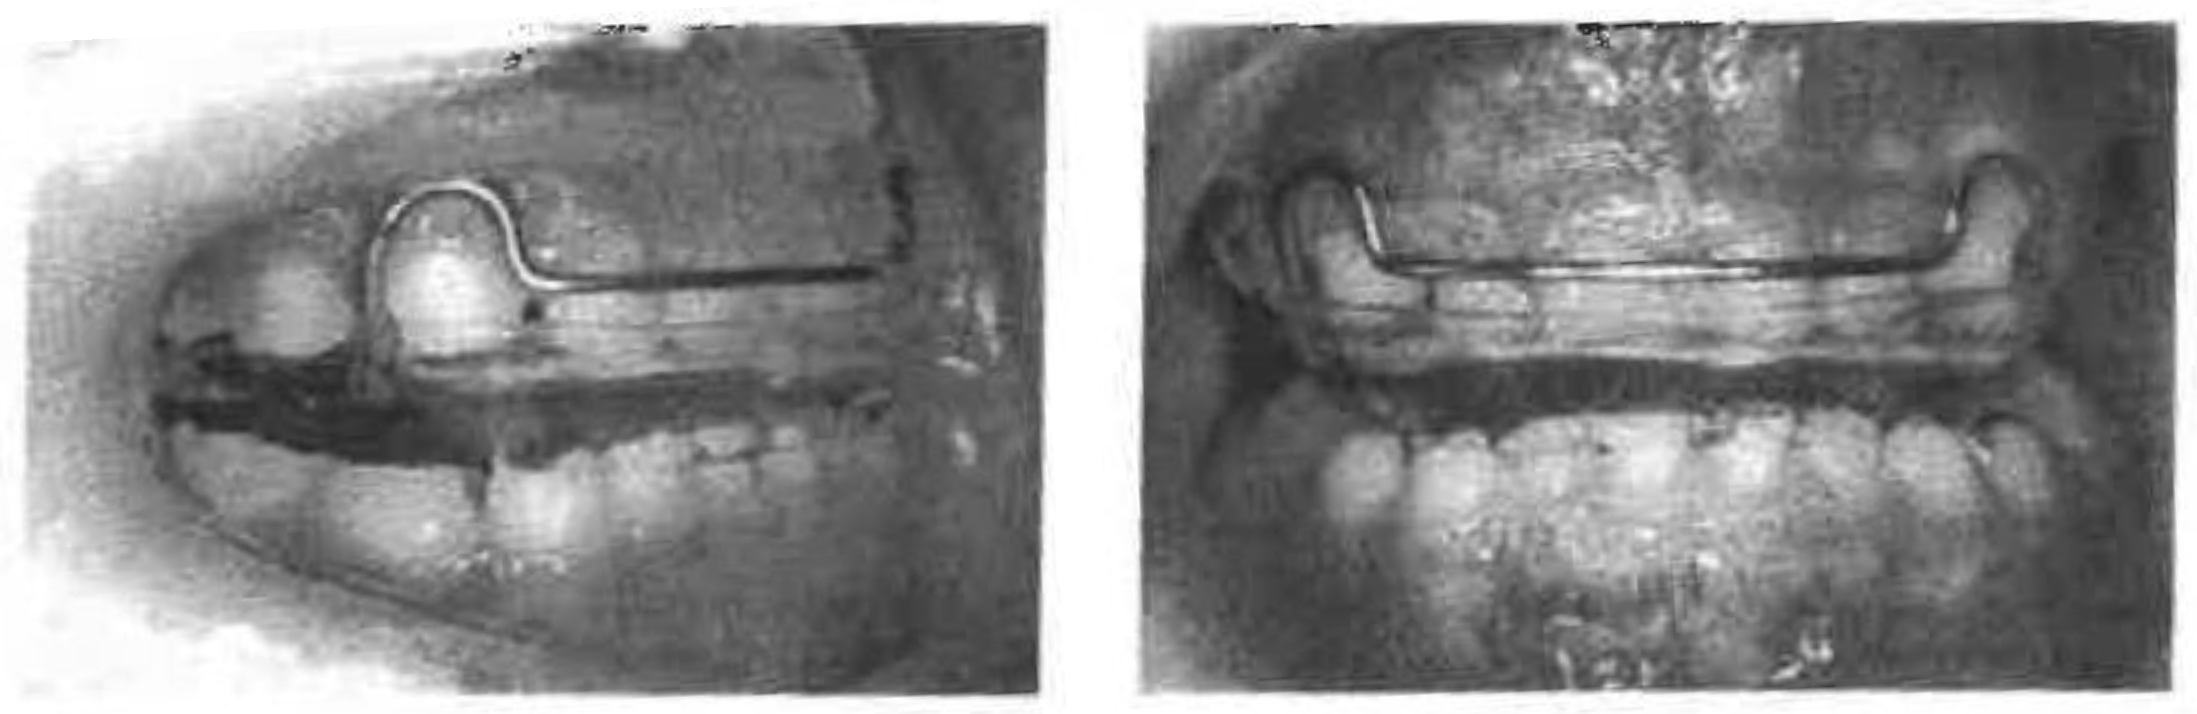

Figure 3. Case 1 - Functional Appliance.

F.A. was worn to reduce the flaring of the upper deciduous central incisors and to stimulate forward mandibular growth in Phase I (Figure 3). The construction bite of F.A. was prepared to create about 3mm of anterior open bite and unforced forward positioning of the mandible. F.A. was adjusted every 2 to 3 months. The child was instructed to wear the appliance at nighttime and as much as possible while at home during the day. Maxillary protrusion was improved in 5 months, resulting in complete elimination of lip sucking and lip biting. F.A. was then left in place as a retainer to facilitate myofunctional adaptation to the new, post-treatment mandibular position. Another F.A. with expansion screws was fabricated for transverse development of the upper and lower arches to create spaces for permanent teeth in the buccal segments in the mixed dentition. The patient is currently under observation.